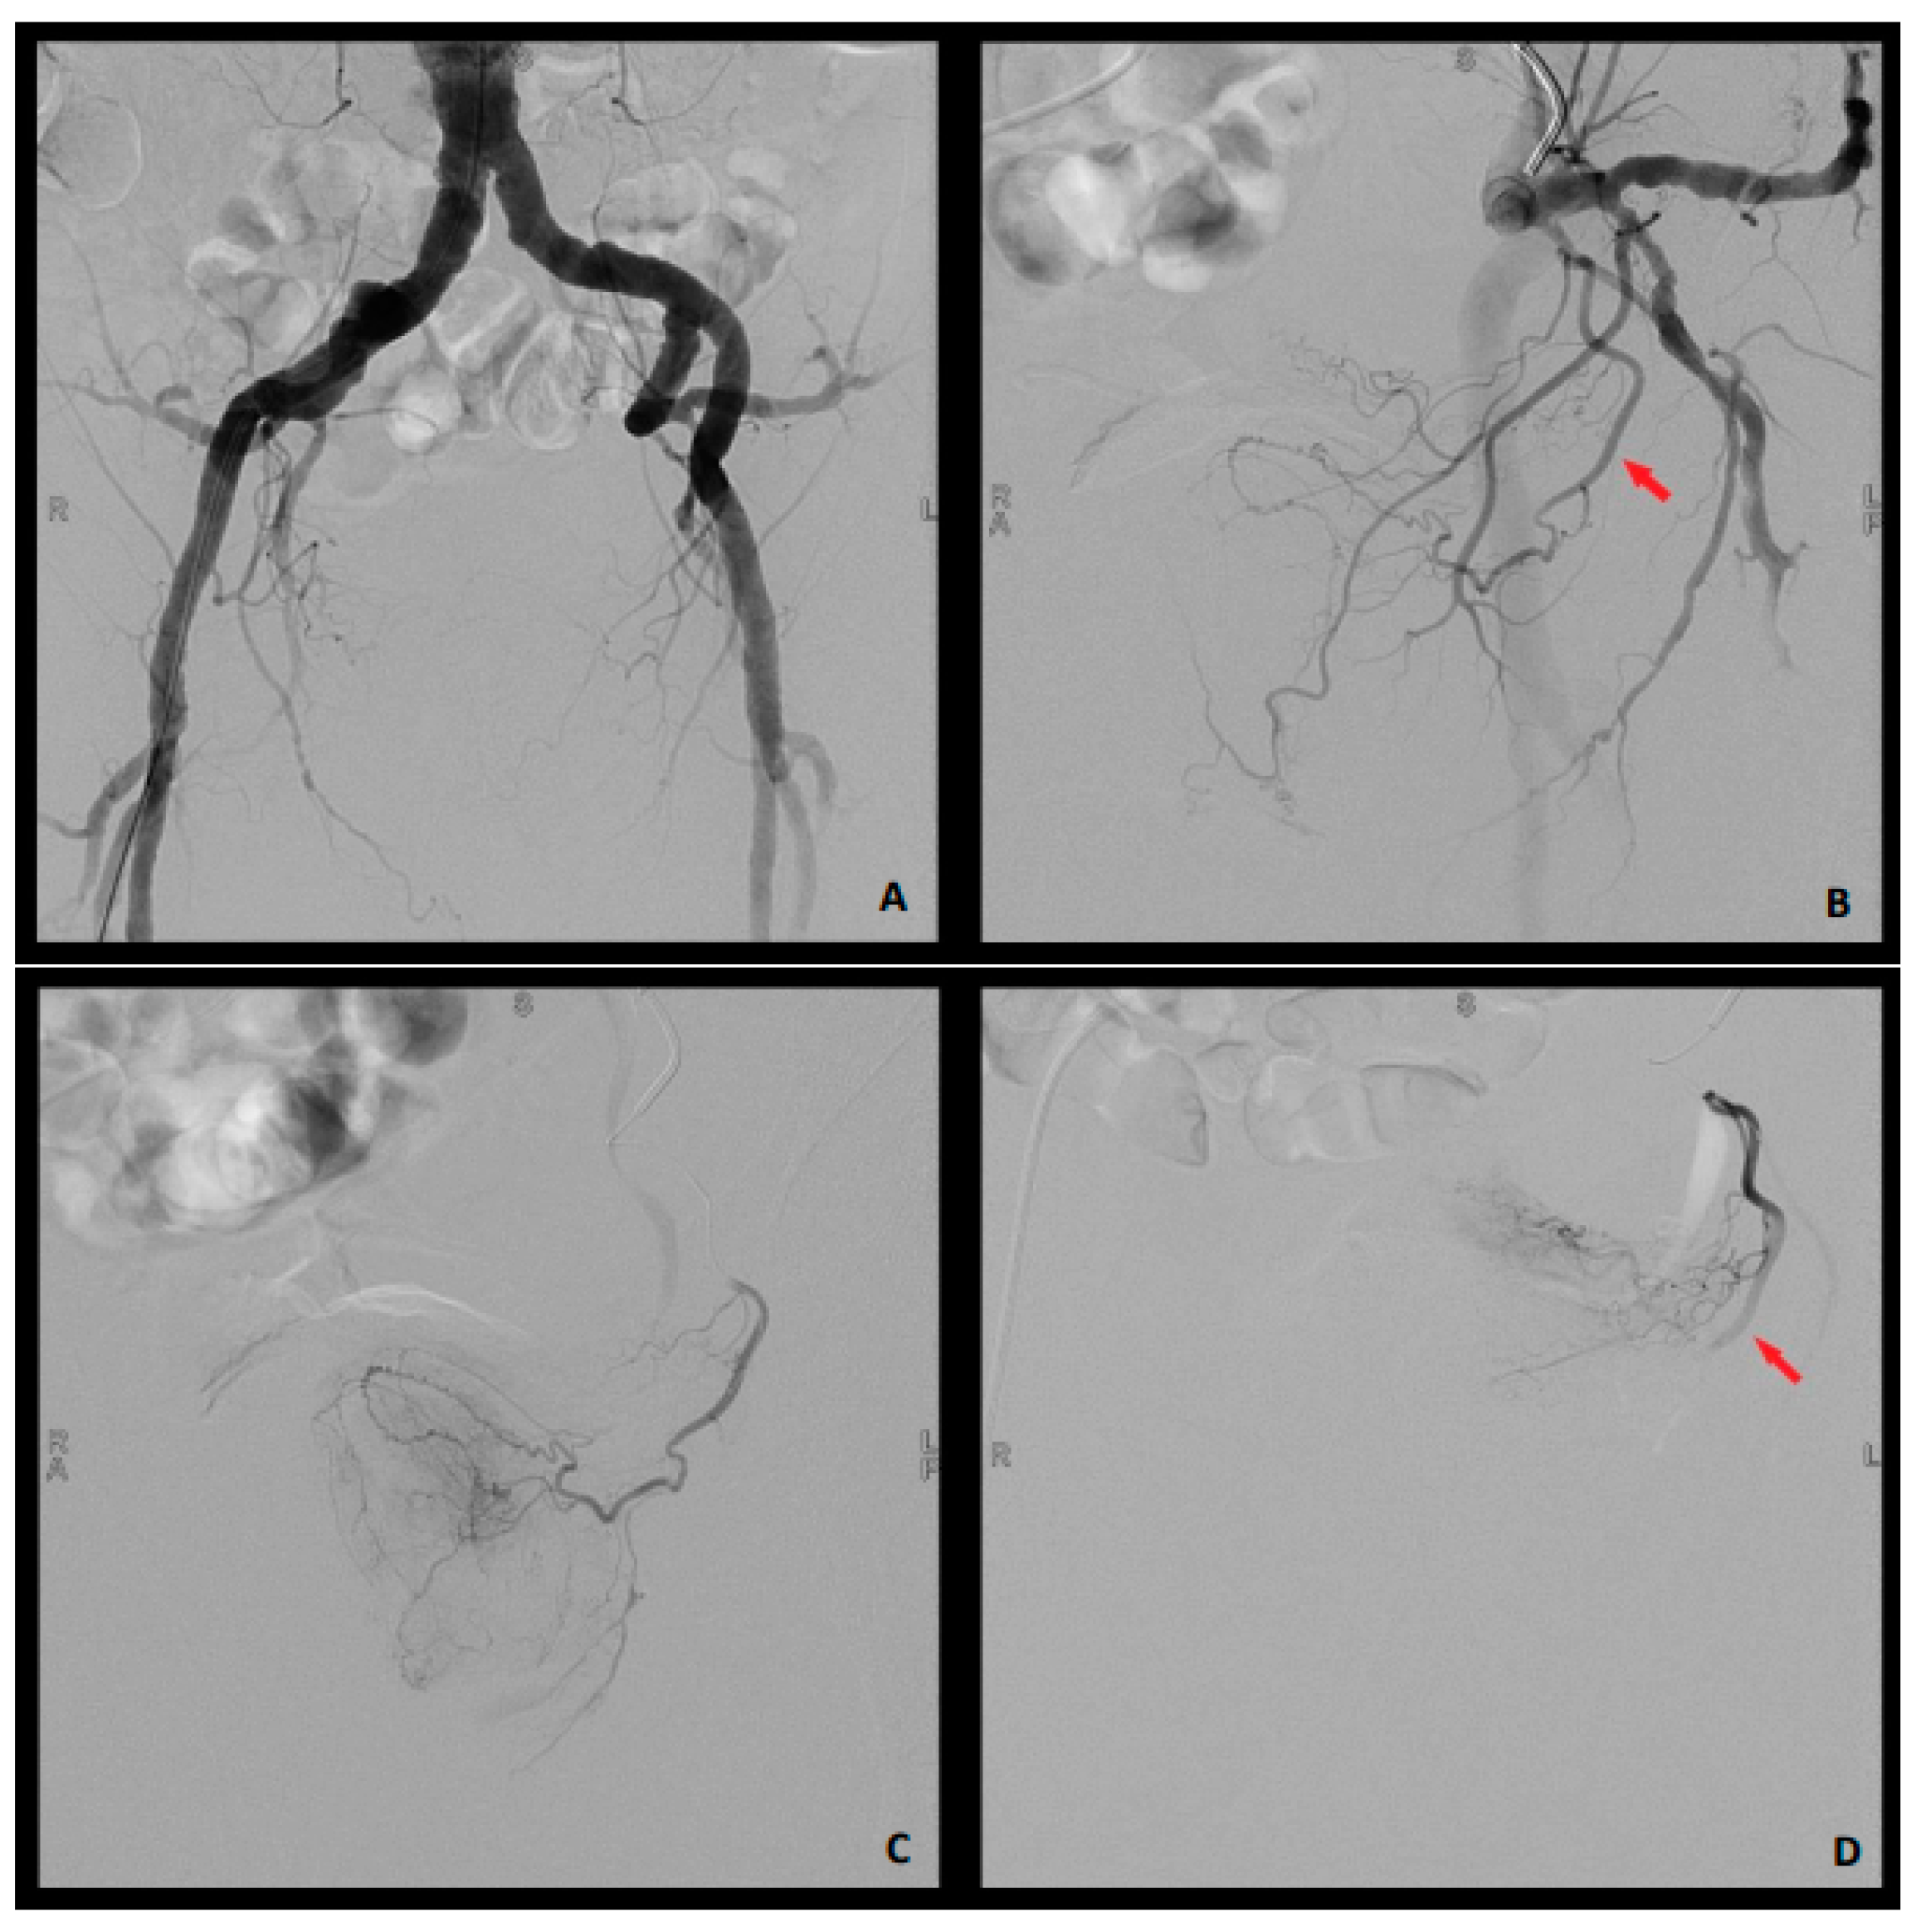

2.2. Embolization Technique